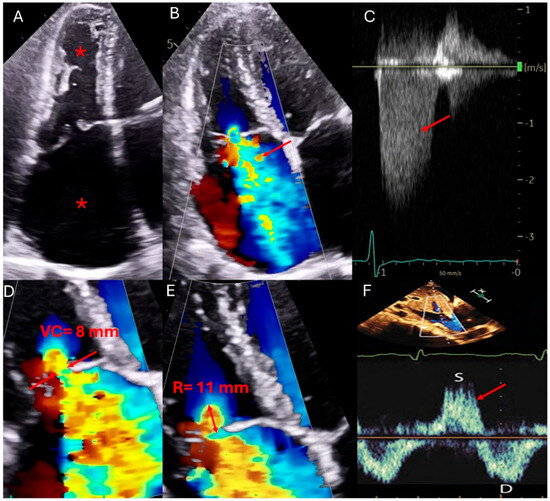

| Transthoracic Echocardiography (TTE) | First-line imaging modality for TR assessment evaluates TR severity, right ventricular function, pulmonary pressures, and inferior vena cava (IVC) size and collapsibility [14,21]. | Widely available, non-invasive, cost-effective. Provides real-time hemodynamic assessment, including TR jet velocity, pressure gradients, and right atrial pressure estimation [14,21]. | Poor acoustic windows in patients with obesity, chronic lung disease, or post-cardiac surgery. Dependent on operator expertise. Subject to interobserver variability [14,21]. |

| Transesophageal Echocardiography (TEE) | Enhanced visualization of the tricuspid valve in cases with poor TTE windows. Useful for assessing leaflet morphology, tricuspid annulus, chordae tendineae, and device-related TR, particularly in patients with cardiac implantable electronic devices (CIEDs) [22,23]. | Superior resolution of valve anatomy and leaflet morphology compared to TTE. Useful for guiding interventions such as transcatheter tricuspid valve repair or replacement. Allows better visualization of prosthetic valve function [22,23]. | Semi-invasive procedure requiring sedation. Limited field of view for evaluating right ventricular function and dependent on transducer positioning for optimal imaging. Potential for esophageal injury or discomfort [22,23]. |